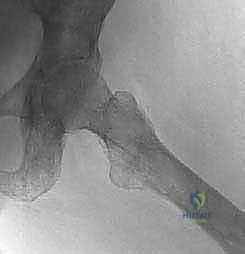

* عنق الفخذ (Femoral Neck): يربط الرأس بجسم العظم. وهو من أكثر الأماكن عرضة للكسور المرضية بسبب النقائل.

* المدور الكبير والمدور الصغير (Greater & Lesser Trochanters): نقاط اتصال عضلات الحوض والفخذ القوية. تدمير هذه المناطق بالسرطان يؤدي إلى عرج شديد وعدم استقرار.

هذا النخاع النشط يوفر بيئة بيولوجية خصبة جداً (تربة غنية بالمواد المغذية وعوامل النمو) للخلايا السرطانية المنتشرة (البذور). بمجرد استقرار الخلايا السرطانية في هذه المنطقة، تبدأ في التكاثر وإفراز مواد كيميائية تتداخل مع الدورة الطبيعية لتجديد العظام، مما يؤدي إلى تدمير البنية الهيكلية القوية للعظم، وضعفه الشديد، وبالتالي زيادة الخطر بشكل مرعب لحدوث ما يُعرف بـ "الكسور المرضية" (Pathologic Fractures) - وهي كسور تحدث نتيجة إجهاد بسيط لا يكسر العظم السليم عادةً.